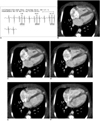

Fig. 2

Effect of slice thickness on image quality of non-ECG-synchronized spiral CT in 12-year-old boy with pulmonary atresia and ventricular septal defect after Rastelli operation.

A. Volume-rendered CT image reconstructed from thin, overlapped axial images with 0.6-mm slice thickness at collimation of 0.6 mm appears quite grainy. That is because slice thickness is too thin at employed CT dose and this thin slice consequently increases image noise enough to degrade image quality. There are two ways to improve image quality in this situation: one is to slightly increase slice thickness and the other is to increase radiation dose a lot.

B. Slight increase in slice thickness to 0.75 mm substantially improves image quality of volume-rendered CT image. This strategy is highly recommended because its dose saving effect is great.